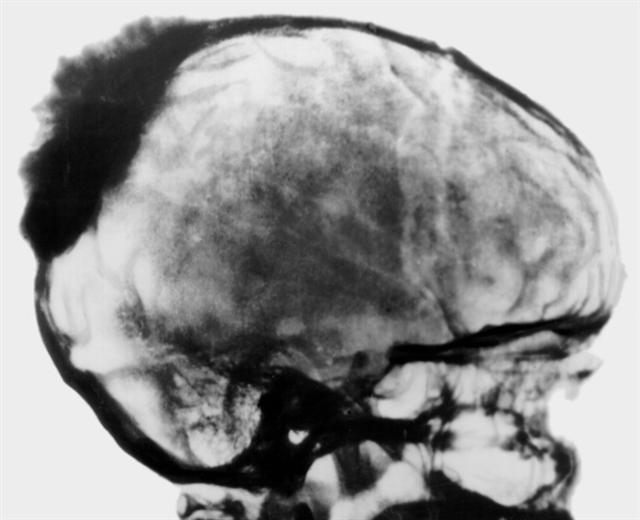

Рис. 9. Боковая рентгенограмма черепа больного при остеогенной саркоме теменно-затылочной области: плотная тень опухоли с выраженной периостальной реакцией в виде веерообразно расходящихся неравномерных спикул.